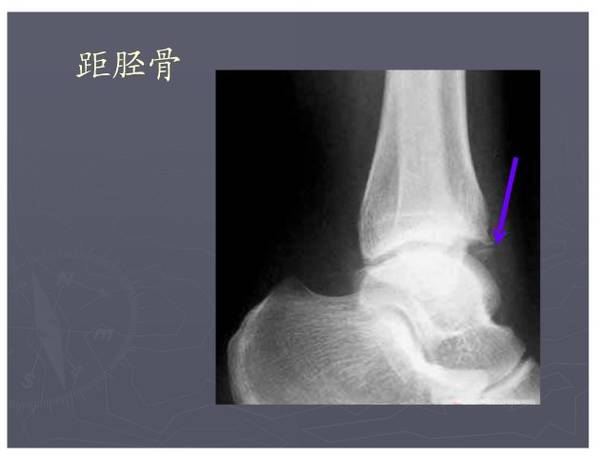

常见异常副骨或籽骨